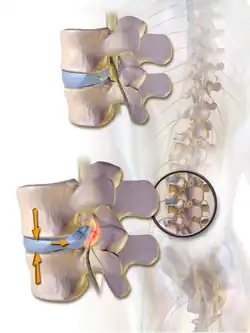

En diskusprolaps er en ryglidelse, hvor en udposning af kernen i en diskus presser mod rygmarvskanalen.